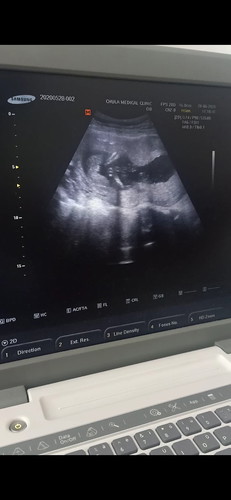

ซาวตอน17w

แบบนี้ใช่เพศหญิงไหมค่ะ มีสิทธิ์ไปเป็นชายไหมค่ะ อยากได้ผู้หญิงมาก